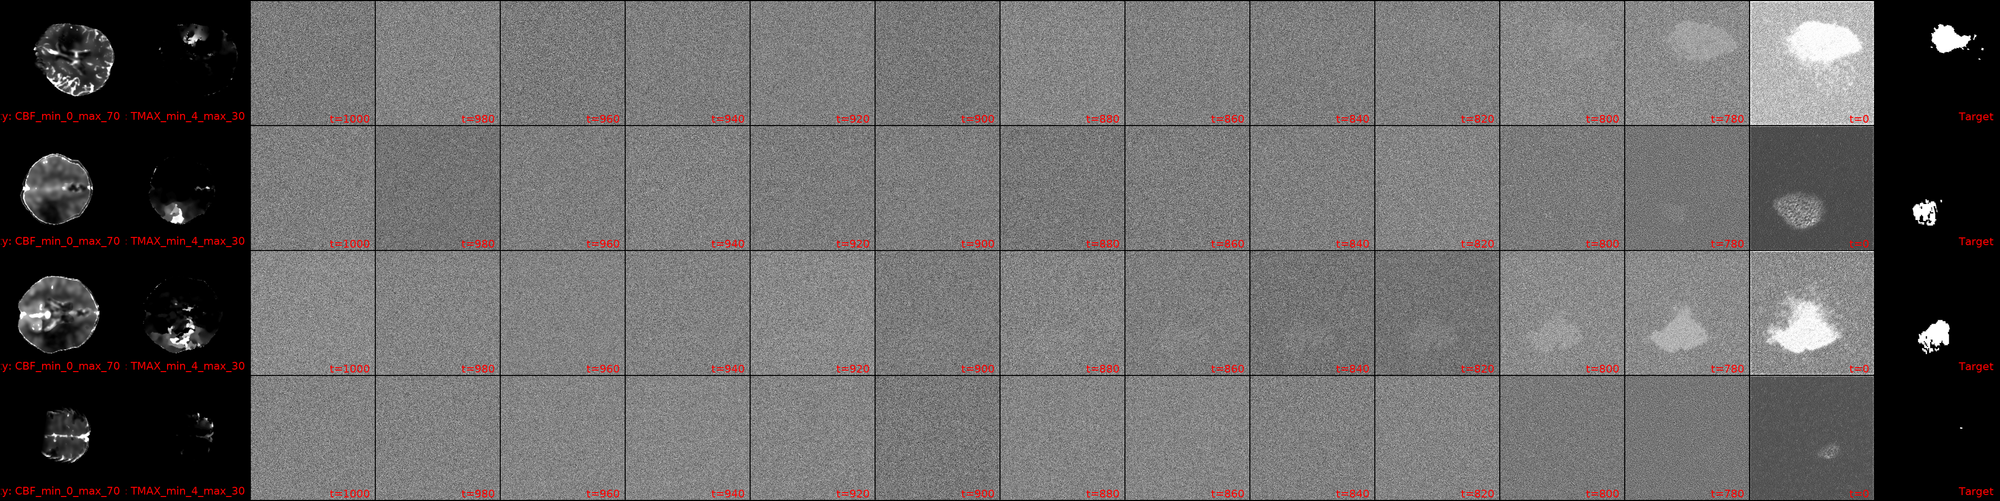

It is at this point that the post's title image comes into play. This is my first training run of a large model (specifics will be discussed in a later, probably next, post) with DDIM reverse diffusion, with 1000 timesteps, but a respacing of the timesteps to 250 (reducing the compute load by 4x). The image, for now, contains a bug from the days of having trained using only 100 timesteps, but this will be fixed shortly (in case you happen to read this in the interim, 👋). But what you can see, is how I have image masks generated via diffusion that dont look absolutely useless! Now, there's still a lot to tune here: the images being fed, augmentations, the model architecture can and will be updated, the learning rate annealing parameters tuned and the diffusion parameters as well, but for the first time, we have Sparks of Diffusion. ⚡